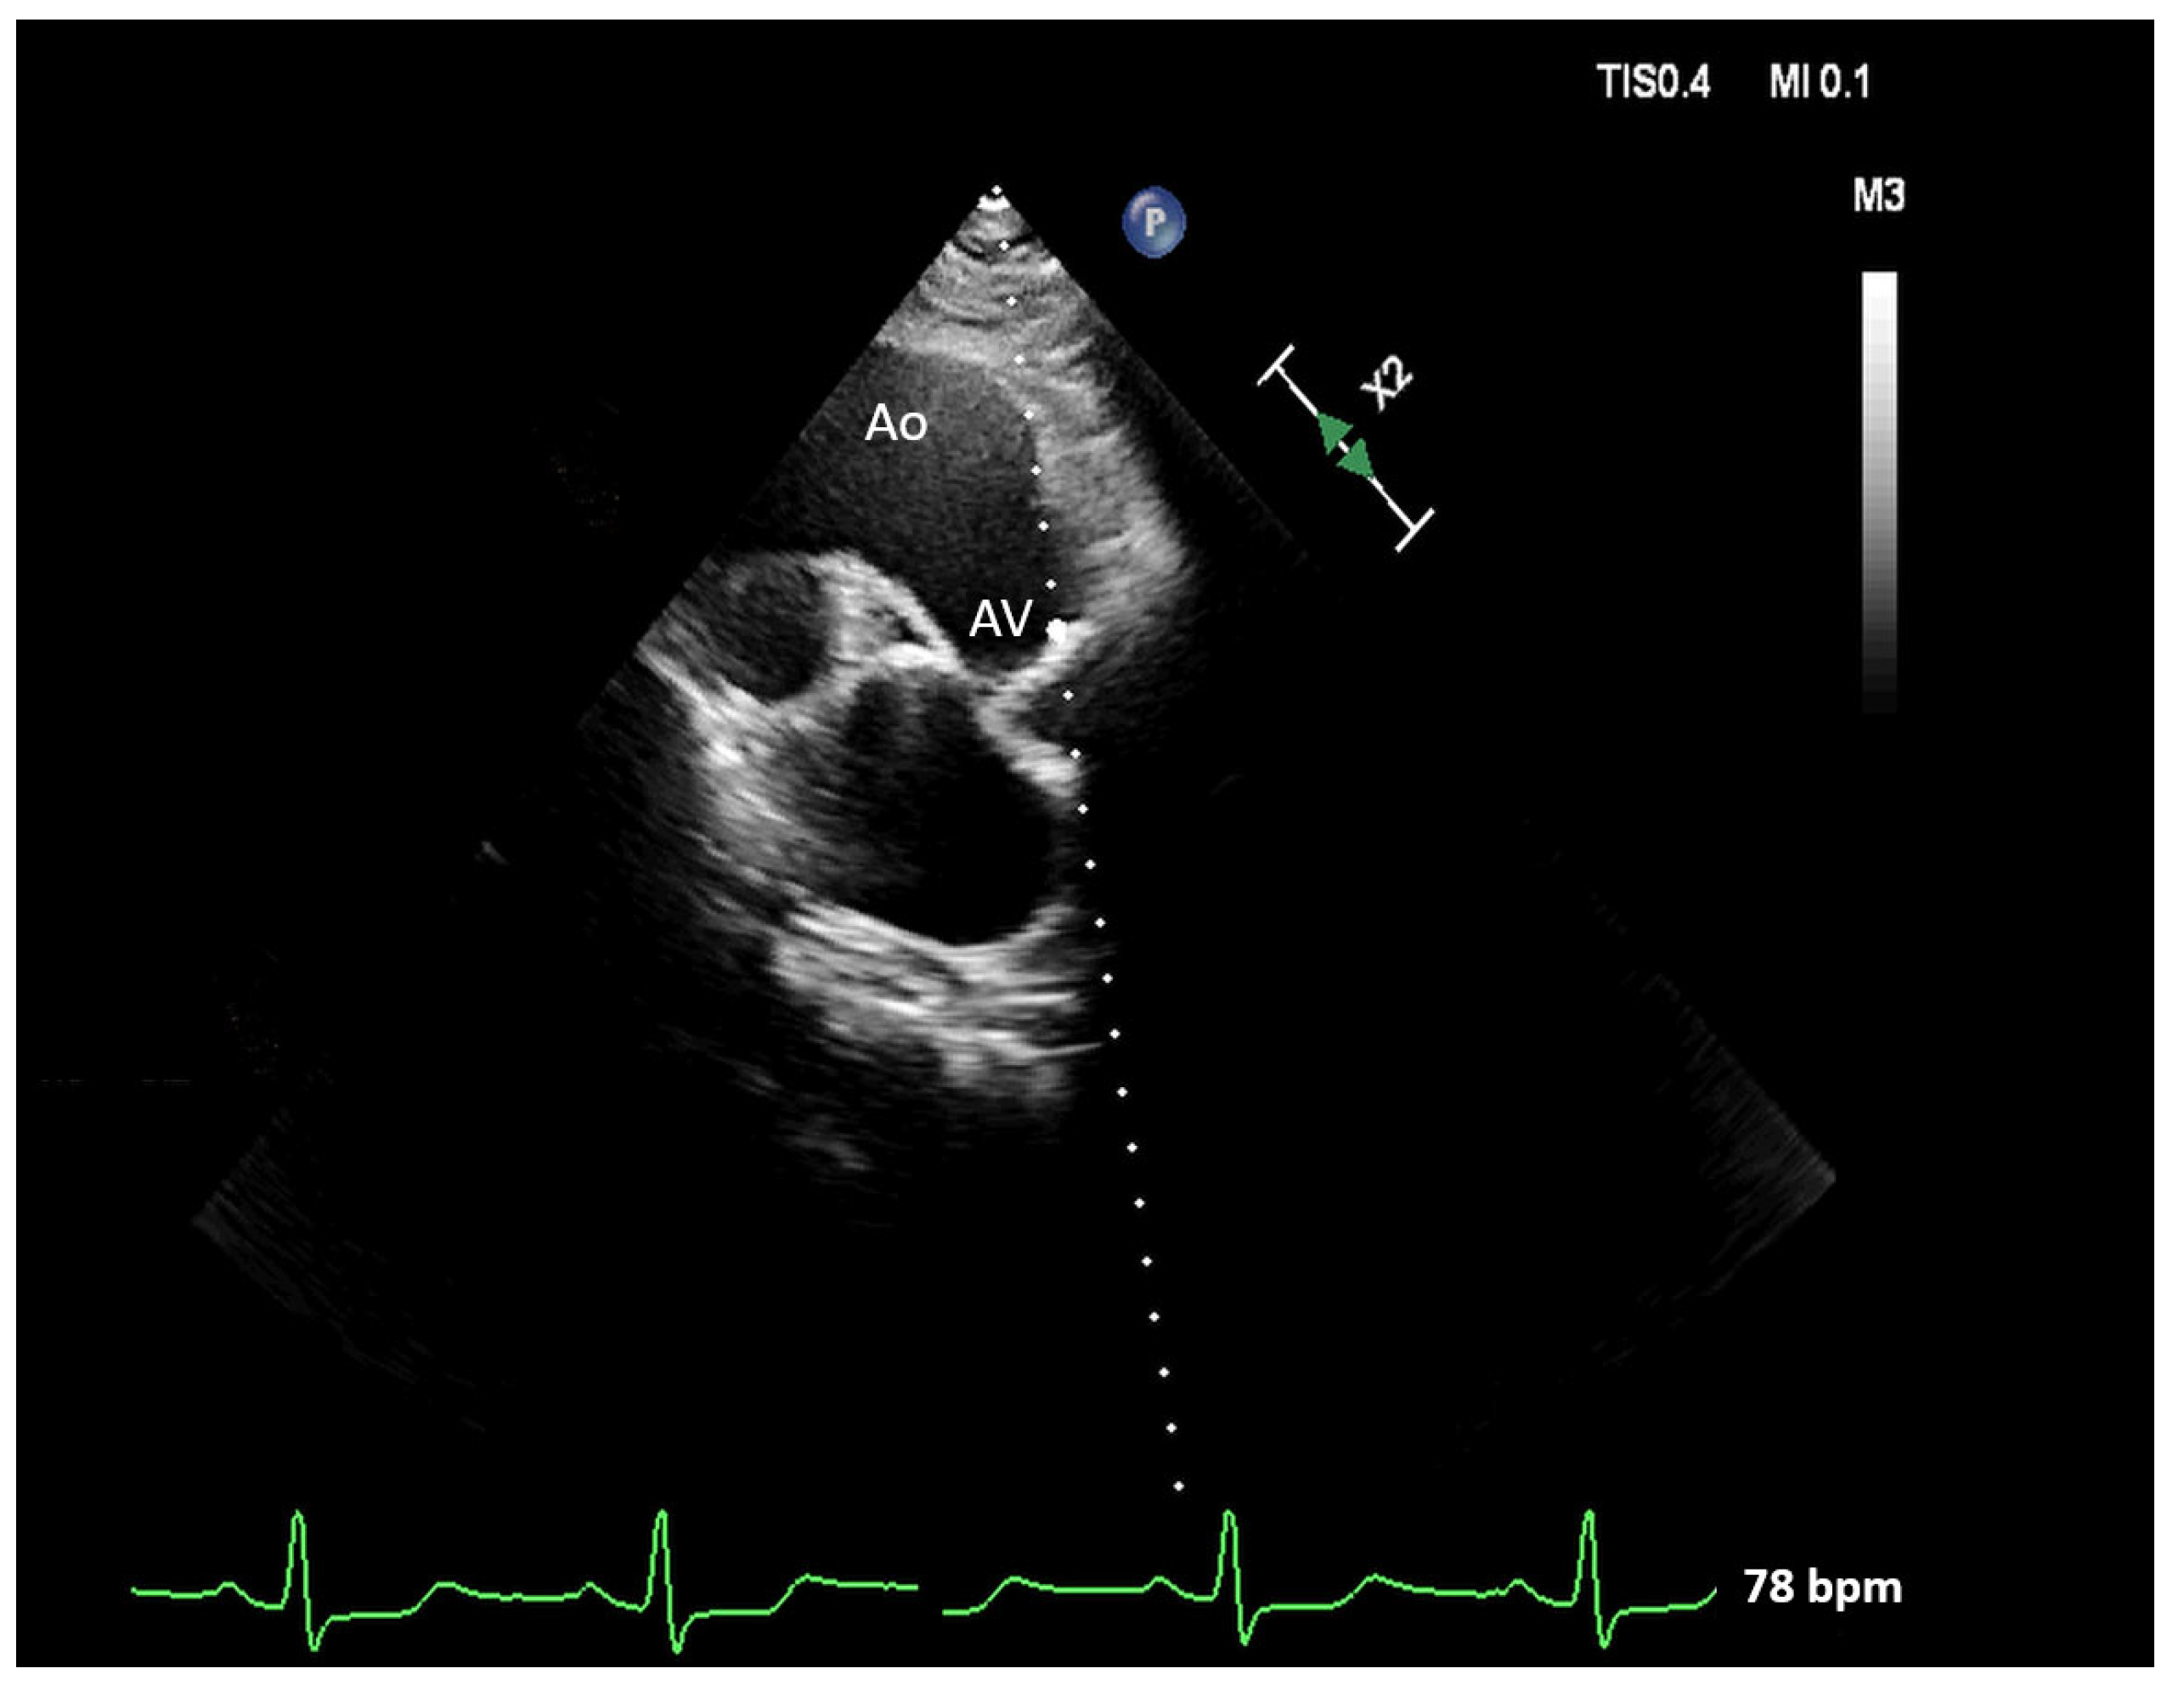

2.2. Multiple-View Scanning of the Aortic Valve

| Ao | aorta |